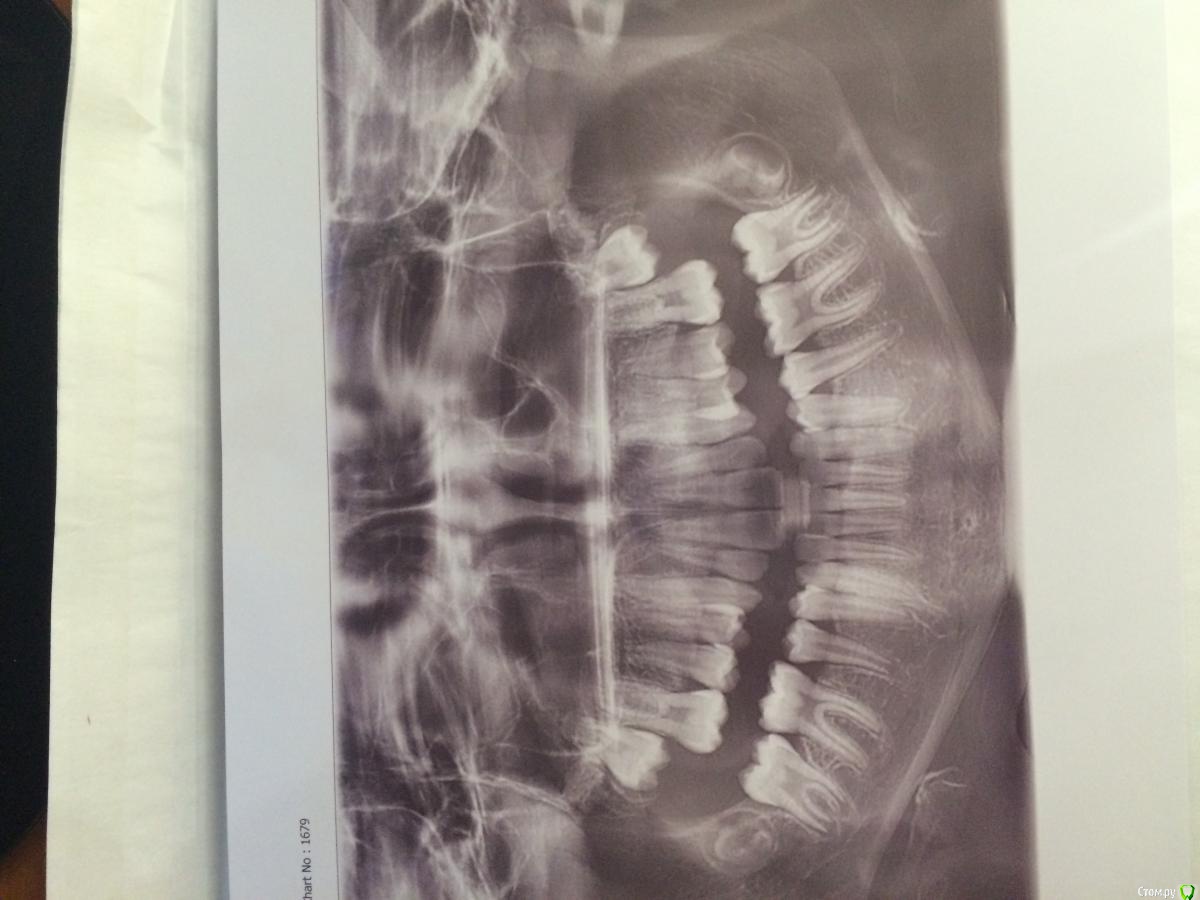

Irina2408 Опубликовано 13 марта, 2016 Поделиться Опубликовано 13 марта, 2016 Добрый день, уважаемые стоматологи. Оцените, пожалуйста, состояние зубов по снимку. Требуется ли лечение? Ребенку 12 лет. Спасибо. Ссылка на комментарий

Джима Опубликовано 13 марта, 2016 Поделиться Опубликовано 13 марта, 2016 Я не вижу ничего плохого. Но оценивать здоровье зубов по ОПТГ - дурное дело, она малоинформативна. Ссылка на комментарий

Brigita Опубликовано 14 марта, 2016 Поделиться Опубликовано 14 марта, 2016 по опг зубы выглядят здоровыми. В чем проблема Ваша? Ссылка на комментарий

Irina2408 Опубликовано 14 марта, 2016 Автор Поделиться Опубликовано 14 марта, 2016 Спасибо за ответ. Да проблем, как таковых, нет. Есть небольшие точки коричневого цвета на зубах, сделали снимок, подумала, что будет не лишним. Хотя может и не надо в таком возрасте? А так как к стоматологу попадаем только в среду, решила здесь проконсультироваться. Ссылка на комментарий

red_butler Опубликовано 14 марта, 2016 Поделиться Опубликовано 14 марта, 2016 Есть небольшие точки коричневого цвета на зубах, сделали снимок, подумала, что будет не лишним. если при очном осмотре все ОК, то снимок это гипердиагностика и он лишний Ссылка на комментарий

IvanK Опубликовано 16 марта, 2016 Поделиться Опубликовано 16 марта, 2016 Выглядит все хорошо Я считаю, что снимок не лишний Ссылка на комментарий